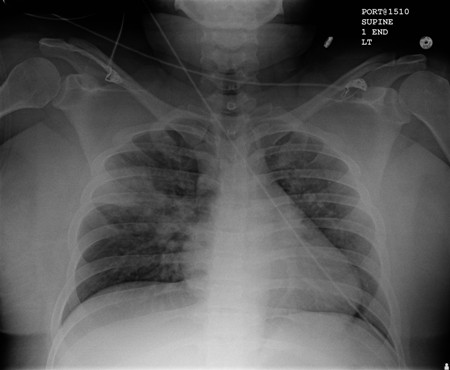

Radiografía de tórax portátil con opacidades bibasales, peor a la derecha que a la izquierda, en un paciente con neumonía adquirida en el hospital

De la colección personal del Dr. F. W. Arnold, División de Enfermedades Infecciosas, Departamento de Medicina, University of Louisville School of Medicine